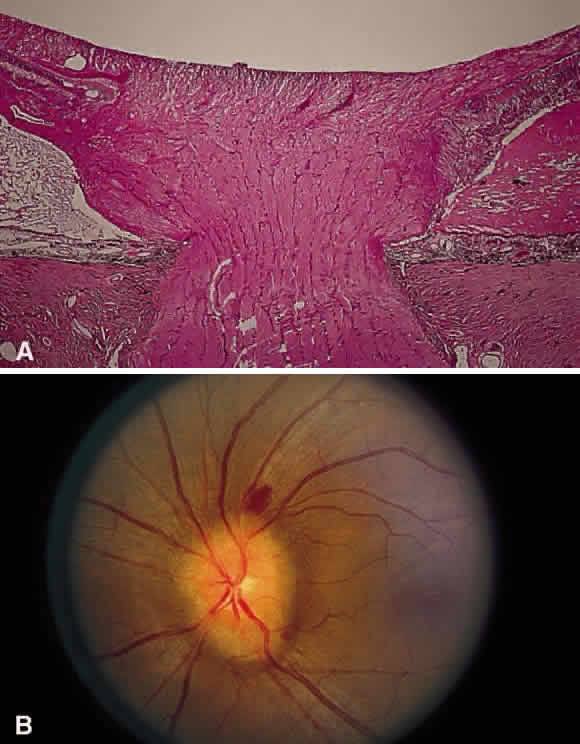

Fig. 30. A. Photomicrograph of an optic disc with papilledema. There is edema of the

disc surface, some engorgement of the vessels, and lateral displacement

of the photoreceptor elements, which results in enlargement of the

blind spot in papilledema. B. Early papilledema in a patient with pseudotumor cerebri. The disc margin

is blurred, the surface slightly elevated, and a small hemorrhage is

present superiorly. (A, courtesy of Ralph C. Eagle Jr, MD, Philadelphia, PA) Fig. 30. A. Photomicrograph of an optic disc with papilledema. There is edema of the

disc surface, some engorgement of the vessels, and lateral displacement

of the photoreceptor elements, which results in enlargement of the

blind spot in papilledema. B. Early papilledema in a patient with pseudotumor cerebri. The disc margin

is blurred, the surface slightly elevated, and a small hemorrhage is

present superiorly. (A, courtesy of Ralph C. Eagle Jr, MD, Philadelphia, PA)